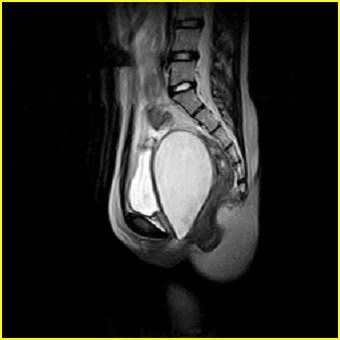

女、15岁、下腹疼痛2天,排尿困难1天。查体:处女膜闭锁,距处女膜约4至5cm处扪及一约5cm直径的圆形包块,张力较高,触痛明显、欠活动。b超提示子宫增大伴宫内增强回声团。

影像意见:子宫直肠陷凹积血。

更正影像意见:阴道积血。

处女膜闭锁,阴道积血

处女膜闭锁,阴道积血,子宫积血.

先天性处女膜闭锁,伴阴道积血,不除外先天性阴道粘液囊肿形成。

阴道积血,子宫积血.

子宫及阴道积血。

处女膜闭锁,伴子宫及阴道积血.